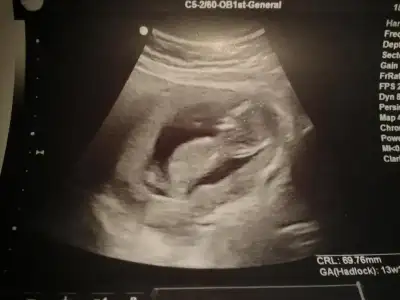

$2013-08-11 22.44.32.webp

kızlar benim resimlerede bi yorum yapın ne acaba?ben anlayamadım.çabuk yazın çok merak ediyorum:49: